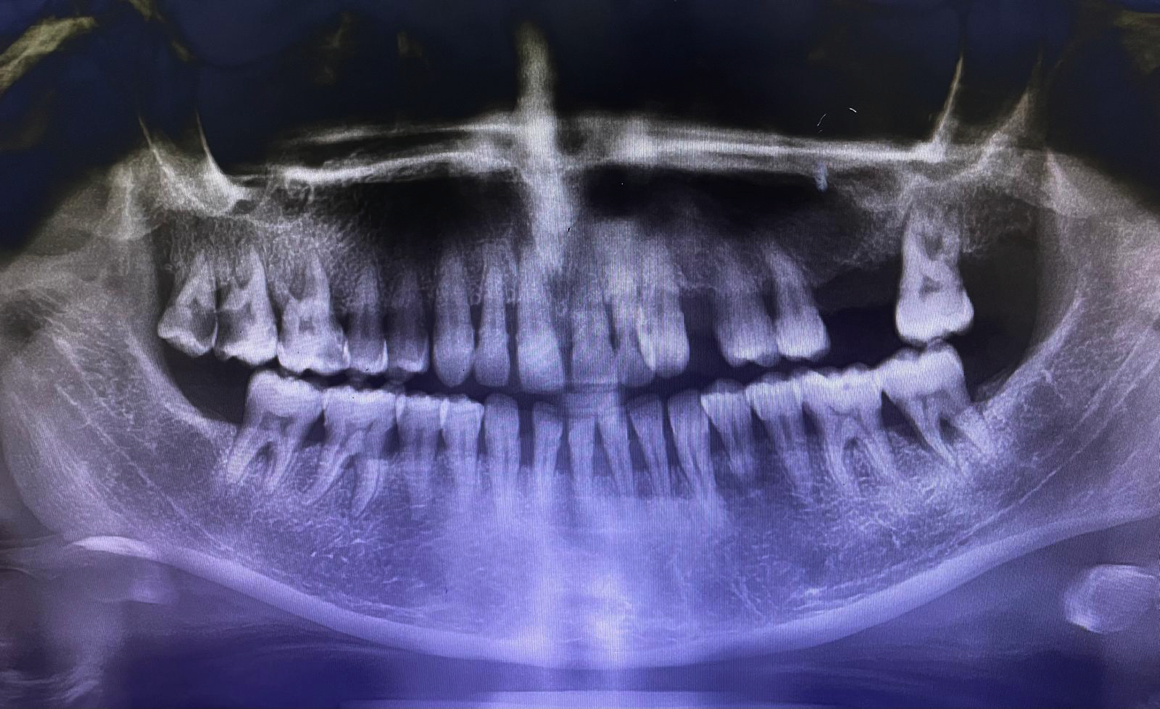

Soğuk çekmeli Grad-4 saf titanyumun gücü, İspanyol tasarım vizyonuyla buluşuyor. En karmaşık cerrahi vakalarda bile yüksek primer stabilite ve hızlı osteointegrasyon için tasarlandı.

Standart titanyumdan %20 daha yüksek tork direnci sağlayan Soğuk Çekme (Cold-Drawn) teknolojisiyle üretilmiştir. Sıfır hata" toleransı ile üretilen gövde yapısı, implantın ömrünü ve mekanik dayanıklılığını maksimuma çıkarır.

Soğuk çekme tekniğiyle üretilen Grad-4 saf titanyum, standart implantlara göre %20 daha yüksek tork direnci ve dayanıklılık sunar.